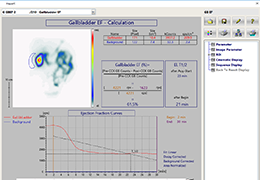

ANYTHINK 经导管主动脉瓣膜置换术分析系统